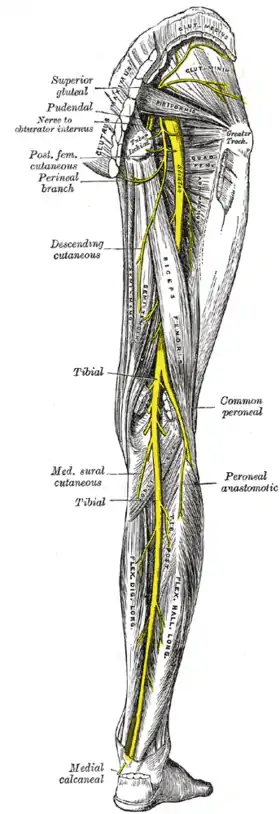

In humans, the sciatic nerve is formed from the L4 to S3 segments of the sacral plexus, a collection of nerve fibres that emerge from the sacral part of the spinal cord. The lumbosacral trunk from the L4 and L5 roots descends between the sacral promontory and ala and the S1 to S3 roots emerge from the ventral sacral foramina. These nerve roots unite to form a single nerve in front of the piriformis muscle. The nerve passes beneath piriformis and through the greater sciatic foramen, exiting the pelvis.[1]: 422–4 From here, it travels down the posterior thigh to the popliteal fossa. The nerve travels in the posterior compartment of the thigh behind (superficial to) the adductor magnus muscle, and is itself in front of (deep to) the long head of the biceps femoris muscle. At the popliteal fossa, the nerve divides into its two branches:[1]: 532

- The tibial nerve, which travels down the posterior compartment of the leg into the foot

- The common fibular nerve (also called the common peroneal nerve), which travels down the anterior and lateral compartments of the leg into the foot

The sciatic nerve supplies sensation to the skin of the foot, as well as the entire lower leg (except for its inner side). Sensation to skin to the sole of the foot is provided by the tibial nerve, and the lower leg and upper surface of the foot via the common fibular nerve.[1]: 422–4

The sciatic nerve also innervates muscles. In particular:[1]: 422–4

- Via the tibial nerve, the muscles in the posterior compartment of the leg and sole of the foot (plantar aspect).[lower-alpha 1]

- Via the common fibular nerve, the muscles in the anterior and lateral compartments of the leg.[lower-alpha 2]

Structures surrounding left hip-joint. Nerves of the right lower extremity. Posterior view.

Nerves of the right lower extremity. Posterior view. Sciatic nerve.